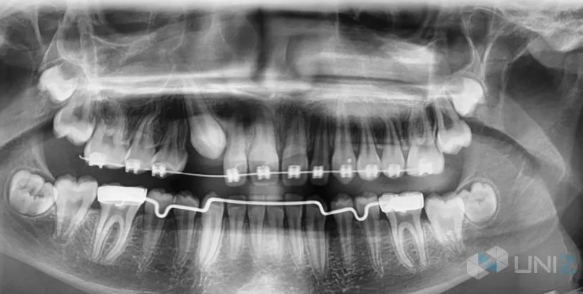

每個人都希望有一口整齊潔白的牙齒,越來越多的人選擇齒科正畸矯正。傳統(tǒng)的正畸矯正方式主要以鋼絲矯正器來治療,這種治療方式非常不美觀,口腔衛(wèi)生護(hù)理較難,而且金屬矯正器可能會刮破嘴唇并造成感染。

隨著科技的進(jìn)步,隱形矯正技術(shù)逐漸進(jìn)入人們的視野。隱形矯正技術(shù)會根據(jù)每個人的不同牙齒結(jié)構(gòu)進(jìn)行量身定制,做出透明的隱形矯正牙套,隱形牙套維護(hù)方便,可自行摘戴,不影響社交、進(jìn)食和運(yùn)動。

學(xué)員可以學(xué)到從口腔掃描,到治療方案設(shè)計、3D打印牙模、熱吸塑成型牙套、后處理及佩戴的全套隱形矯正流程。該課程為期兩年,不光學(xué)習(xí)理論知識,還會親手進(jìn)行實(shí)踐操作,最大特點(diǎn)是課程中既包含最新的隱形矯正教學(xué)方案,同時也包含傳統(tǒng)的鋼絲矯正教學(xué),讓學(xué)員可以同時掌握兩種不同的矯正技術(shù)。

UNIZ科技的SLASH PLUS 3D打印機(jī),憑借打印速度快,精度高等集成優(yōu)勢,成為EOMAC現(xiàn)代正畸學(xué)院的首選正畸教具。其他3D打印機(jī)打印模型需要兩三個小時,學(xué)生無法當(dāng)堂看到打印效果,更無法當(dāng)堂利用打印的模型來做練習(xí)。但SLASH PLUS卻可以在13分鐘內(nèi)快速打印出6個牙模,真正做到“當(dāng)堂講課,當(dāng)堂練習(xí)”,極大提升了學(xué)習(xí)效果和效率。